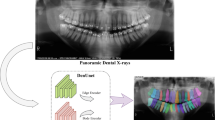

In clinical practice, accurate dental plaque segmentation plays an important role in the diagnosis of oral problems such as dental caries and periodontitis. Existing methods consistently exhibit undesired structural distortions owing to the intensive variations in shape and the ambiguous boundaries of the plaques. In this paper, we introduce a Structure-Preserving Dynamic Complementary Interaction Network (SPDINet) that facilitates complementary information interaction between main plaque segmentation sub-network and auxiliary boundary sub-network to address this problem. Mutual-attention module (MA) and gradient guided refinement module (GGR) achieve this dynamic interaction at the feature level and result level, so as to preserve perceptual-pleasant details and further avoid structural distortion for plaque segmentation. In MA module, A bi-directional cross-task Mutual-attention mechanism reduces misleading attentions and distributes attention responses to emphasize parts that one task overlook while another task highlights. In GGR module, gradient boundaries derived from mask prediction category-wisely refine the boundary probability map to generate a more accurate boundary around the object, which in turns significantly boosts the performance of segmentation and implicitly implements the information interaction. Experiments on two recent dental plaque segmentation datasets, including SDPSeg-S and SDPSeg-C, show SPDINet establishes new state-of-the-art results.